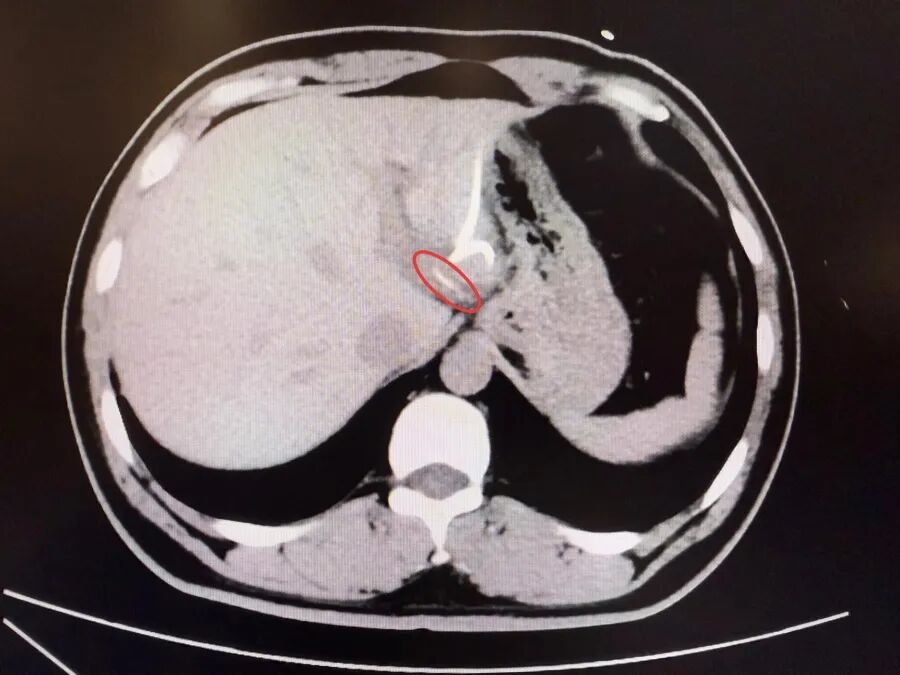

直到行CT檢查時,醫生才驚訝地發現——肝臟左葉靠近胃賁門處,竟有一條細長的高密度影,形似魚刺。原來,那根魚刺在吞咽厚穿透了胃壁,從賁門區域「鑽」入肝臟,引發感染與膿腫。在簡單進行肝膿腫介入穿刺引流后,當地外科醫生評估后認為,要徹底清除異物,需要進行左半肝切除手術,但這對於李先生來說,創傷大、風險高,他難以接受。

而魚刺位置非常兇險,就在賁門旁刺入左肝,緊貼大血管。病程長、腹腔感染粘連嚴重,術中可能找不到魚刺,一旦操作不慎也會造成內鏡下無法控制的大出血。而後醫師提出了個大膽的設想——能否通過胃鏡,在食道管壁夾層建個隧道「開一扇門」,直接進入腹腔取出魚刺?這個想法意味著要讓內鏡「跨越」胃壁的天然邊界,是一次前所未有的嘗試。

經過耐心手術分離,一抹銀光在燈下閃現——那正是長約3.5厘米的魚刺,鋒利如針,已深深嵌入左肝組織中。醫師穩穩夾住魚刺,將其完整取出,全程無明顯出血。手術歷時3小時,患者術後恢復順利,體溫恢復正常,肝膿腫逐漸吸收,免於進行高創傷、高風險的左半肝切除手術,保住了完整的肝臟功能。